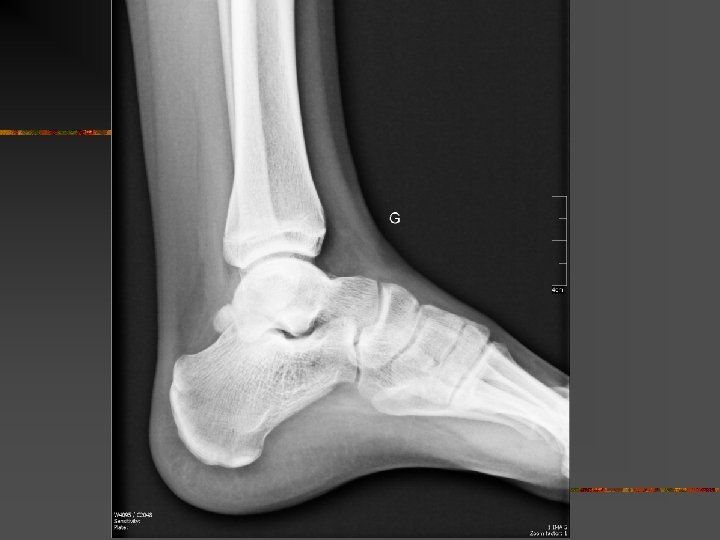

Le SCP traumatique : Mécanismes Trauma en flexion plantaire forcée n Très fréquent… n Origine : Shoot contré, tacles, irrégularité du sol, … Lésions : - contusion « postérieure » chondrales, caps. -ligamentaire - # processus post. lat. du talus (# de SHEPHERD) - # malléole tibiale postérieure - # os trigone ou de la synchondrose n Difficultés : - DD # ou os trigone… - Arguments : - # : trait net et non corticalisé - scintigraphie n

Fracture du processus postéro-latéral